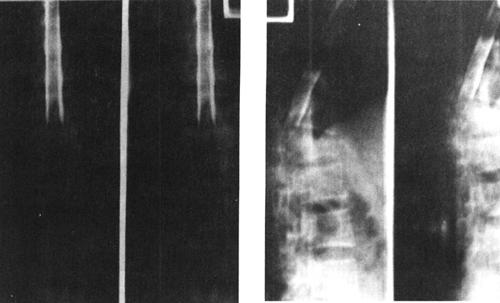

(一)X线平片和X线体层摄影

X线平片是脊柱损伤后的最基本和最重要的影像学检查方法,主要观察脊柱骨折和脱位情况。X线平片具有简单、易行和快速等优点,且可在不搬动疑似急性脊髓损伤患者的情况下在床边拍摄。X线平片空间分辨率高,骨骼结构成像清晰,目前仍是脊柱脊髓损伤检查的首选的影像学检查方法(图7-1)。临床上绝大多数的脊柱创伤骨折、关节脱位和半脱位都可通过普通X线的适当体位的投照而发现(图7-2)。脊柱常规投照位置有前后位、侧位和左、右斜位等。高质量的照片是诊断的最基本条件,如果一次照片不能满足诊断的需要,应调整相应的投照条件、胶片位置、球管中心以及投照角度重复拍摄,直至满意为止。对于怀疑有脊柱脊髓损伤患者应该在尽可能少搬动患者的情况下进行X线照片,尽量避免由于搬动病人而造成脊髓损伤加重。由于X线平片是投照部位解剖结构的重叠图像,限制了对复杂骨结构,特别是中轴骨骼解剖细节的显示,易漏诊细微而重要的骨折和错位。

图7-1 正常颈椎X线侧位片:正常颈椎前、中、后三柱连线光滑连续,中、后柱连线之间为脊髓所在

图7-2 C5以上前脱位,中、后柱连线显示在C5水平处明显狭窄,表明颈髓在此处受压